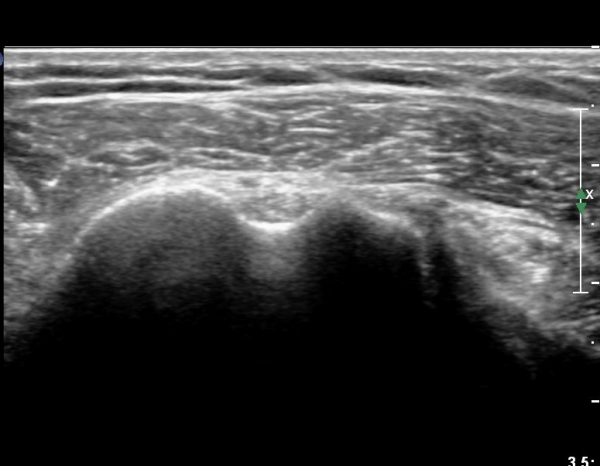

ŽÃËÀÚ¸¦ ¾à°£ °ßºÀ ¸»´ÜÀ¸·Î ³»¸®³ª ¿À±¸µ¹±â°ßºÀÀδëÀÇ ¼®È¸È­°¡ °üÂûµÈ´Ù(»çÁø 2).